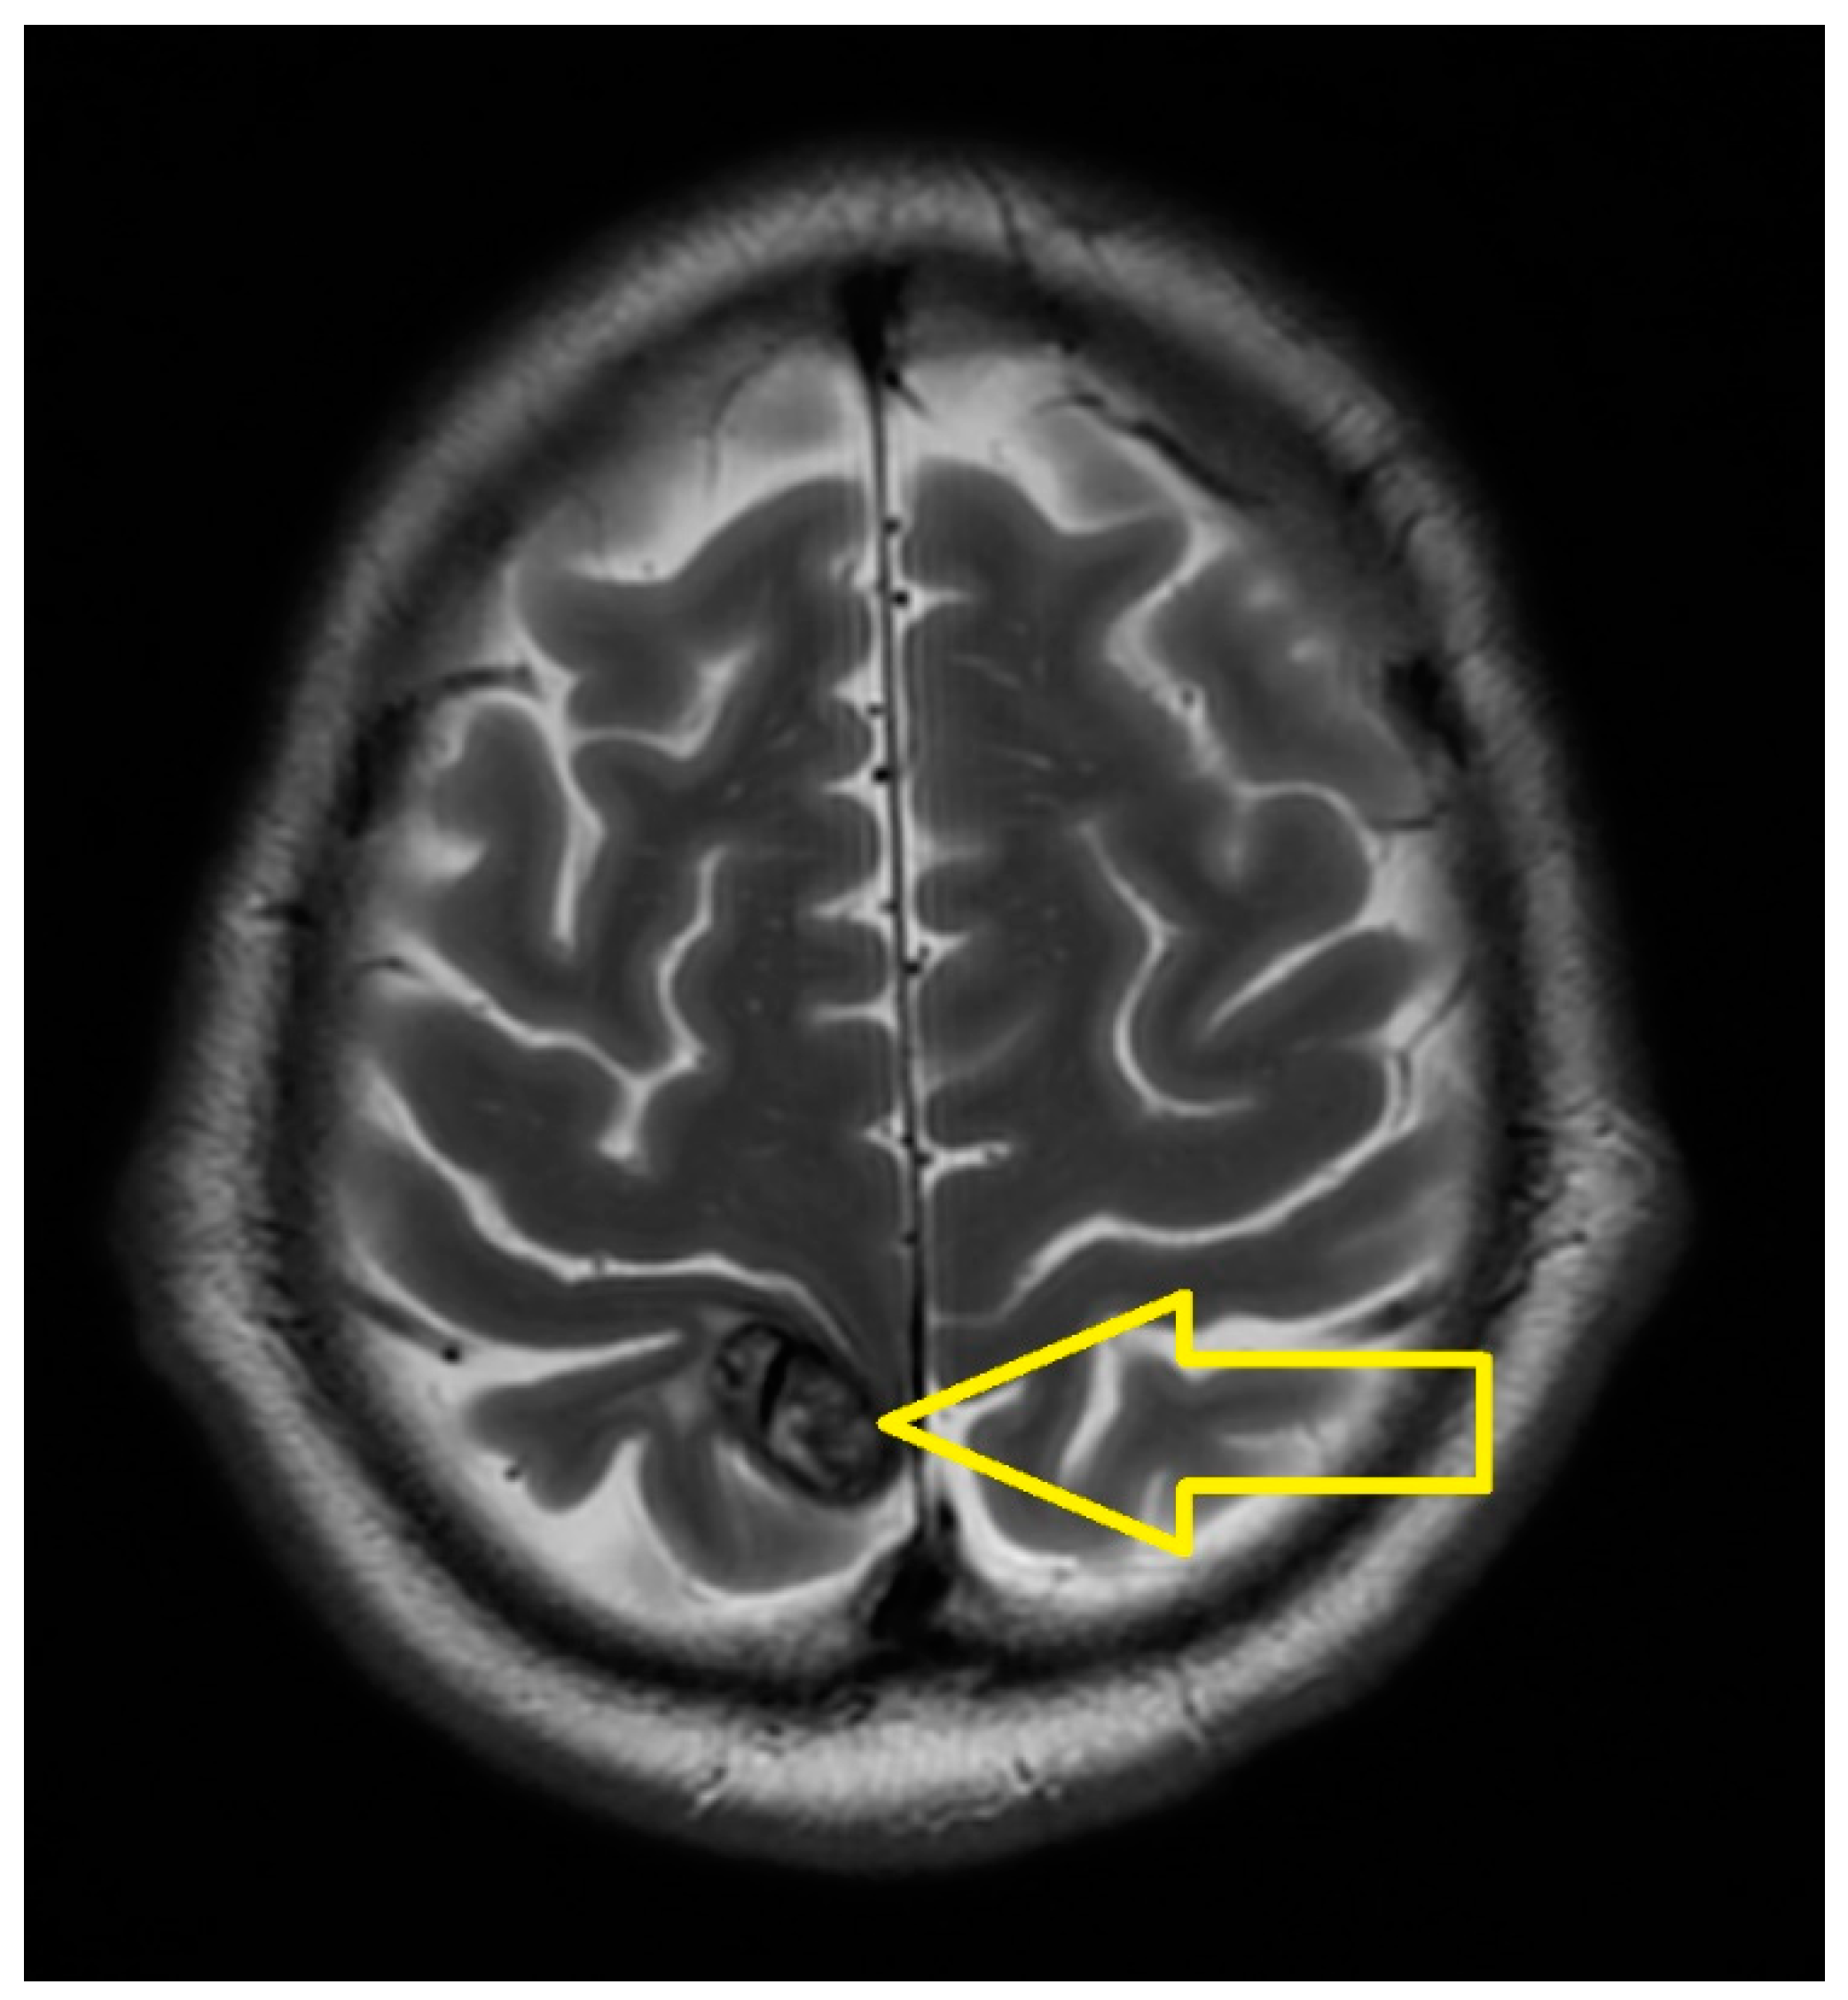

2. Case Presentation